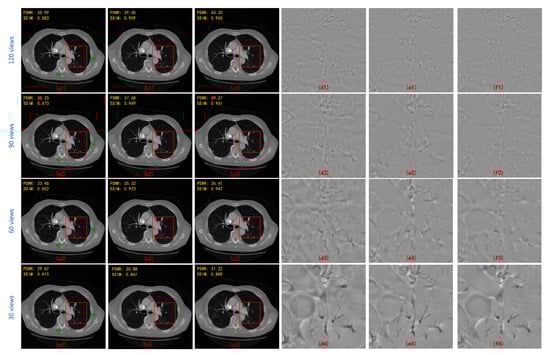

- On the basis of single domain restoration, a hybrid domain reconstruction model for sparse-view CT is proposed, which consists of a projection completion module in radon domain and an image restoration module in image domain. Wavelet domains of projection data and image data are embedded in two modules respectively to better extract spatial features and recover texture details. Moreover, the proposed model is end-to-end learning through the differentiable FBP operator.

- Multi-level wavelet packet decomposition is utilized to replace the pooling operator and enlarge the effective receptive field. Experimental results have shown that a multi-resolution network with a multi-level wavelet transform can effectively suppress globally distributed streaking artifacts.

- A deep residual learning framework is proposed to learn artifacts. Once the artifacts are estimated, an artifact-free image can be obtained by subtracting the estimated results.